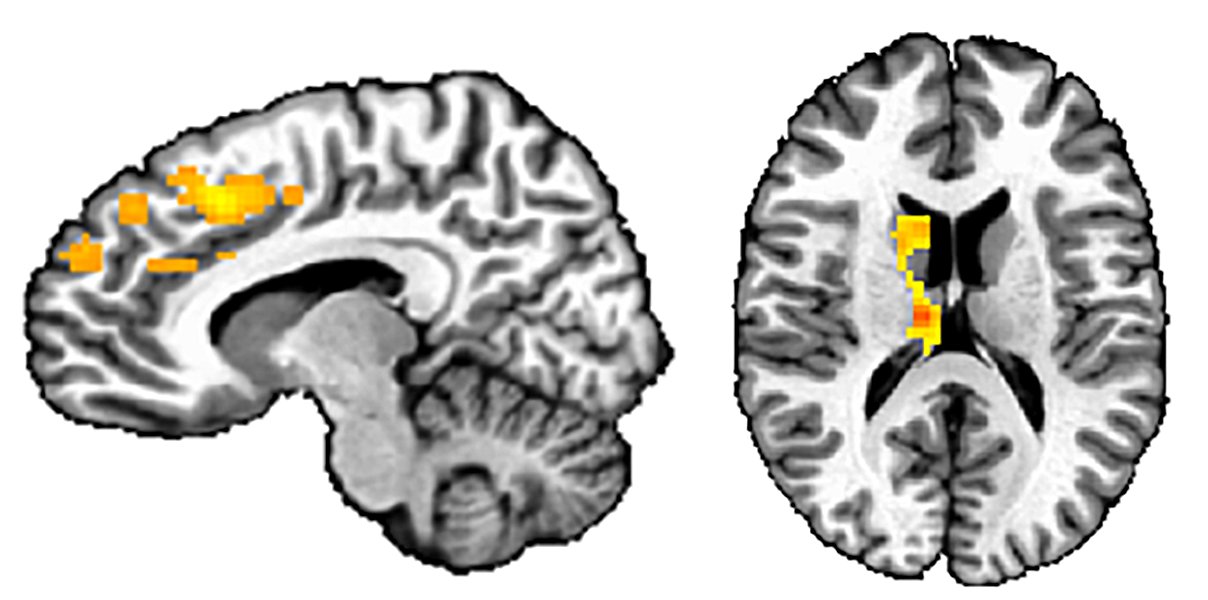

Functional magnetic resonance imaging (fMRI) studies, which use scans to observe brain activity, have affirmed the notion that children with severe irritability respond differently to frustration. One 2019 study compared 134 children between 8 and 18 who had irritability and a diagnosis of DMDD, anxiety disorder or ADHD, with 61 non-irritable volunteers. As they lay in the MRI scanner, the children played a game, earning up to 50 cents for every target they hit — until the researchers intentionally frustrated them by deducting winnings, explains coauthor Wan-Ling Tseng, a developmental neuroscientist at Yale School of Medicine.

Though irritable and non-irritable kids reported similar levels of frustration, the brains of irritable children responded differently: They showed heightened activity in the striatum, a brain region important for processing rewards, as well as in the prefrontal cortex, key to regulating emotions and executing tasks. Some other studies have also hinted at unusual activity in the emotion-processing amygdala in frustrated kids, though Tseng’s study didn’t observe this.

To Tseng, the prefrontal cortex findings suggest that in irritable kids, prefrontal cortices need to work harder to focus. “It’s more effortful for them,” she says. (After the game, the children were given $25 to take home, in addition to their compensation for participating, so that they left with a positive experience.)